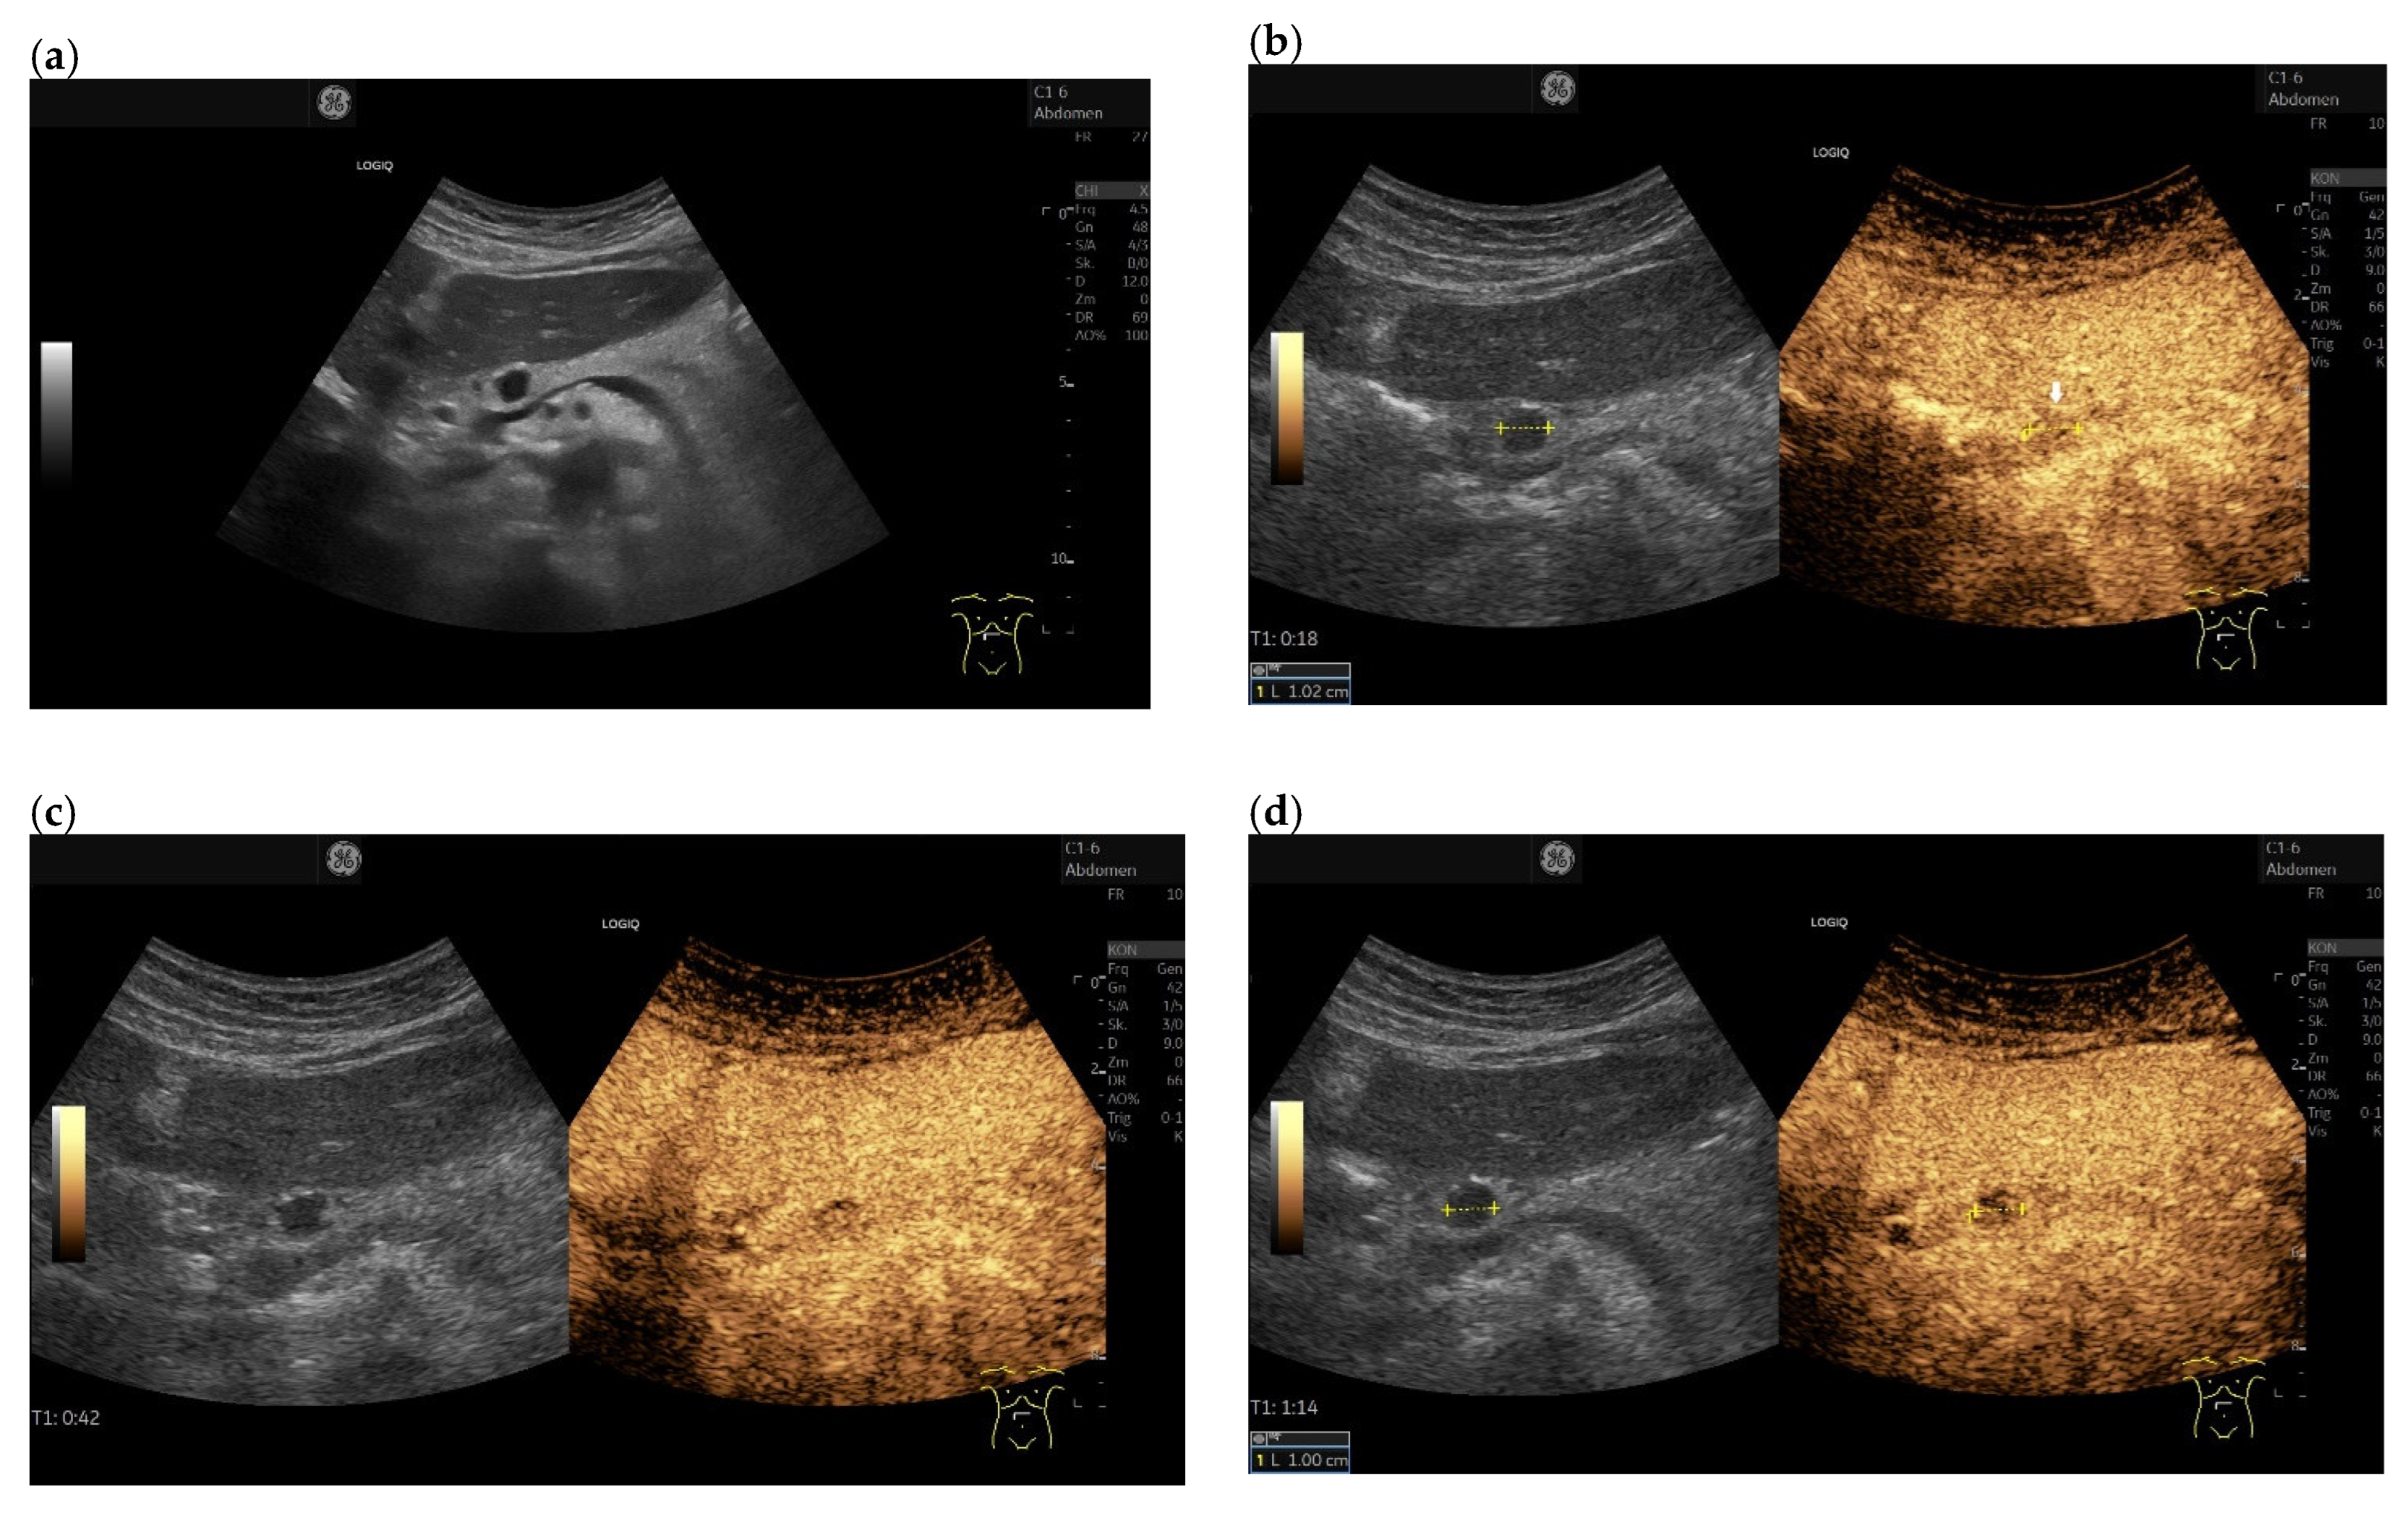

3.3. US and EUS

3.4. CEUS and CH-EUS

B-mode US/EUS

| Mostly hypoechoic, homogeneous, or heterogeneous More likely well-defined borders (46%) Anechoic and hyperechoic lesions are possible | Hypoechoic, typically heterogeneous, irregular borders | Hypoechoic, mostly homogeneous, smoothly bordered. Cystic components or cystic solid PanNENs are possible |

| Variable, in 80% no pancreatic duct dilatation | Pancreatic duct stenosis and pancreatic duct dilatation are an early and typical feature | No pancreatic duct dilatation |

| Mostly no infiltration into adjacent vessels | Infiltration around and into the vessels | No infiltration into adjacent vessels |

| Colour Doppler Imaging | RCC metastases are hypervascularized Most other pancreatic metastases are hypovascularized | No hypervascularization | Hypervascularized |

| Elastography (small lesions up to 15 mm) [67] | 41% softer or isoelastic, 59% stiffer compared to pancreatic parenchyma | 4% soft or isoelastic, 96% stiffer compared to pancreatic parenchyma | 64% soft or isoelastic, 36% stiffer compared to pancreatic parenchyma |